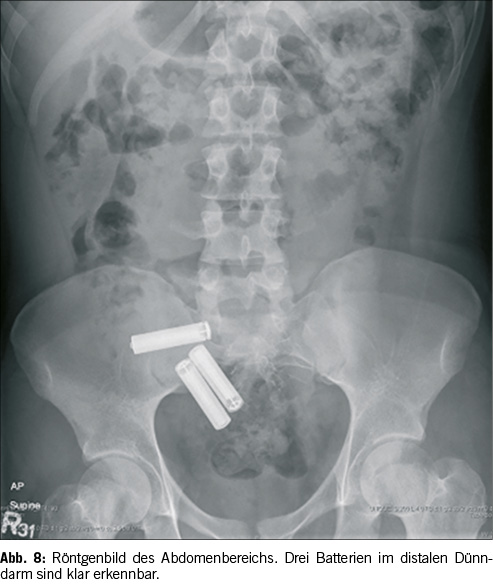

Wichtig zu beachten ist ebenfalls, das sogenannte «Frequent Flyer» Phänomen. Dieses besagt, dass wenn beim Patienten bereits ein Fremdkörper gefunden wurde, die Wahrscheinlichkeit eines Weiteren signifikant erhöht ist. Besonders bei Patienten mit Verhaltensstörungen oder Entwicklungsrückständen ist dies der Fall, da sie oftmals zuvor bereits einen Fremdkörper unbemerkt verschluckt hatten. Primär sind solche Fälle bei Magneten ein grosses Risiko. Patienten verschlucken selten einen einzelnen Magneten, im Schnitt sind es gleich 6-7. Nun besteht die Gefahr einer Darmperforation. Diese wird durch zwei oder mehr Magneten auf beiden Seiten von benachbarten Darmschlingen verursacht. Daraus kann eine Hypomotilität, eine funktionelle Obstruktion oder sogar eine fokale Drucknekrose resultieren. Wird eine Darmperforation nicht rechtzeitig behandelt, kann sie tödlich enden.[4] [10] Neben Magneten geht von ingestierten Batterien die grösste Gefahr aus. Es ist wichtig, dass jede Batterie so schnell wie möglich aus dem Körper entfernt wird. Verbleibt eine Batterie länger innerhalb des Magen-Darm-Traktes besteht die Gefahr, dass die Batterie anfängt «auszulaufen», wobei eine ätzende Substanz austreten kann, welche wiederum eine Verletzung / Entzündung der Schleimhäute, inklusive möglicher Perforation, zur Folge hat. Zusätzlich können Batterien zu Mediastinitis oder Peritonitis führen. Deshalb ist es wichtig, jede Batterie schnellstmöglich zu entfernen.